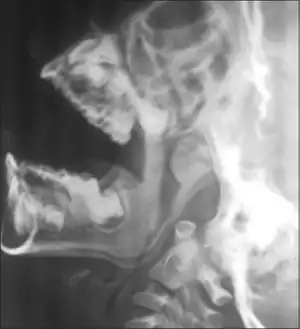

- Posterior rhinoscopy: was used in earlier times; the postnasal space is visualized using a posterior rhinoscopy mirror.

- X-ray lateral view of nasopharynx